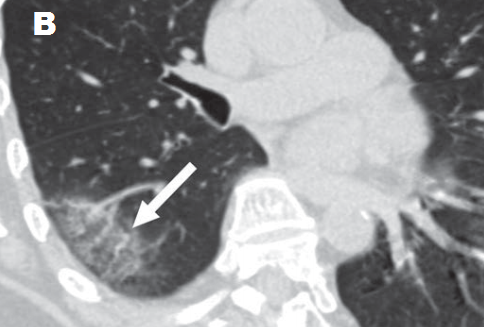

– Pan và cộng sự [6] quan sát ở 21 bệnh nhân được xếp loại thể nhẹ (không có suy hô hấp, không thở máy) thì diễn tiến của bệnh được chia thành 4 giai đoạn tương ứng với biến đổi của các biểu hiện trên hình CLVT: 1/ giai đoạn sớm (0-4 ngày), trong giai đoạn này thì hình ảnh đám mờ kính đục là chủ yếu, diện thương tổn nhỏ; 2/ giai đoạn tiến triển (5 -8 ngày), trong giai đoạn này, viêm nhiễm trở nên trầm trọng và lan rộng hơn, từ biểu hiện đám mờ kính đục xuất hiện thêm biểu hiện lát đá không đều và đặc phổi; 3/ giai đoạn đỉnh điểm (9 -13 ngày), trong giai đoạn này thì tốc độ lan rộng của thương tổn chậm lại, hình ảnh đặc phổi chiếm ưu thế bên cạnh thương tổn đám mờ kính đục lan tỏa và mẫu hình ảnh lát đá không đều, xuất hiện các dải xơ trong nhu mô; 4/ Giai đoạn hấp thu (trên 14 ngày), trong giai đoạn này thì tình trạng viêm nhiễm được kiểm soát, thương tổn đặc phổi được hấp thu dần qua trung gian hình kính đục đơn thuần và không có hình ảnh lát đá không đều, sau đó thì xóa mất hoặc xuất hiện các dải xơ.

– Trong trường hợp diễn tiến xấu đi về mặt lâm sàng thì trên hình ảnh CLVT cho thấy các biểu hiện biến đổi theo hướng gia tăng mức độ trầm trọng; nghiã là thương tổn gia tăng về mặt số lượng, phân bố lan tỏa hơn, số thùy phổi bị tác động nhiều hơn [7,1011,12]; thương tổn gia tăng kích thước, lúc này vị trí thương tổn không chỉ khu trú ở ngoại vi dưới màng phổi mà còn lan dần về phía trung tâm; về mặt đậm độ thì thương tổn các loại có biểu hiện gia tăng đậm độ hơn, với loại thương tổn dạng kính đục thì tăng dần mật độ theo hướng hình thành đám mờ kiểu lát đá không đều (do dày ra của vách liên tiểu thùy và xuất hiện các vách bên trong tiểu thùy phổi) và mô phổi đặc thay thế dần diện kính đục, với loại thương tổn dạng đặc phổi thì đậm độ cũng gia tăng hơn, tạo nên hình ảnh “phổi trắng”, điều này khiến chức năng của phổi suy giảm hẳn. Một điểm đặc biệt là trong tiến triển của thương tổn của viêm phổi COVID-19 không có sự hình thành hốc hoại tử như trong các bệnh lý viêm phổi do nhiễm trùng. Các tiến triển xấu đi của thương tổn thường gặp ở nhóm bệnh nhân già, có bệnh lý nền (hình 4,5) .